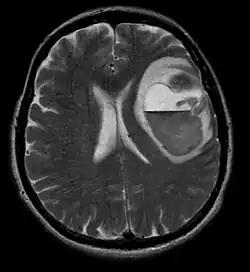

La tomodensitométrie (TDM) et L'imagerie par résonance magnétique (IRM) peuvent détecter efficacement une néoplasie dans le cerveau. L'IRM est plus sensible que la TDM pour identifier les lésions, mais présente des contre- indications pour les patients porteurs de stimulateurs cardiaques, de prothèses incompatibles, de clips métalliques et contre-indications. La TDM reste la méthode de choix pour détecter les calcifications au sein des lésions ou les érosions osseuses de la calotte ou de base du crâne. L'utilisation d' agents de contraste, iodés dans le cas du scanner et paramagnétiques (gadolinium) dans le cas de l'IRM, permet l'acquisition d'informations sur la vascularisation et l'intégrité de la barrière hémato-encéphalique, une meilleure définition de la tumeur tumorale par rapport à l' œdème environnant et à la génération d' hypothèses sur le degré de malignité. L'examen radiologique permet également d'évaluer les effets mécaniques et les modifications importantes des structures cérébrales résultant de la tumeur, telles que l' hydrocéphalie et les hernies, dont les effets peuvent être fatals. Enfin, en préparation à la chirurgie, ce diagnostic peut être utilisé pour déterminer la localisation de la lésion ou l'infiltration de la tumeur dans des zones vitales du cerveau. À cette fin, l'IRM est plus efficace que la tomodensitométrie car elle peut fournir des images en trois dimensions.

Les outils d'imagerie radiologique diagnostique mettent en évidence la modification du tissu néoplasique par rapport au parenchyme cérébral normal (par le biais de modifications de la densité tissulaire imagée électroniquement en TDM et de l'intensité du signal en IRM). Comme la plupart des tissus pathologiques, les tumeurs sont également reconnaissables par une accumulation accrue d'eau intracellulaire. Dans la tomodensitométrie, ils apparaissent hypodenses, c'est-à-dire de moindre densité que le parenchyme cérébral, dans la tomographie par résonance magnétique nucléaire avec relaxation spin-réseau hypointense et en relaxation spin-spin ainsi que l' hypersignal en pondération protonique (PD).

La tomodensitométrie du cerveau montre généralement une masse tissulaire qui peut être améliorée par l'un ou l'autre contraste. Au scanner, les gliomes de bas grade apparaissent généralement isodenses au parenchyme normal et peuvent donc ne pas présenter de rehaussement de contraste. De même, les lésions de la fosse crânienne postérieure sont difficiles à identifier au scanner. Par conséquent, les seuls résultats d'une telle tomographie ne sont pas toujours suffisants à des fins diagnostiques. Dans les cas douteux, l'utilisation de l'imagerie par résonance magnétique plus sensible est indispensable.

Sur-L'IRM montre une tumeur intracrânienne comme une lésion massive qui peut devenir plus luminescente après utilisation du produit de contraste. Cependant, il y a toujours une anomalie de signal dans -L'imagerie par résonance magnétique, qui indique la présence d'une néoplasie ou d'un œdème vasogénique. Habituellement, une luminescence accrue (amélioration du contraste) indique une tumeur d'un grade supérieur de malignité. Un anneau de contraste est caractéristique du glioblastome, avec la partie luminescente correspondant à la partie vitale de la tumeur maligne, et la plus foncée - zone hypointense correspondant à une nécrose tissulaire.